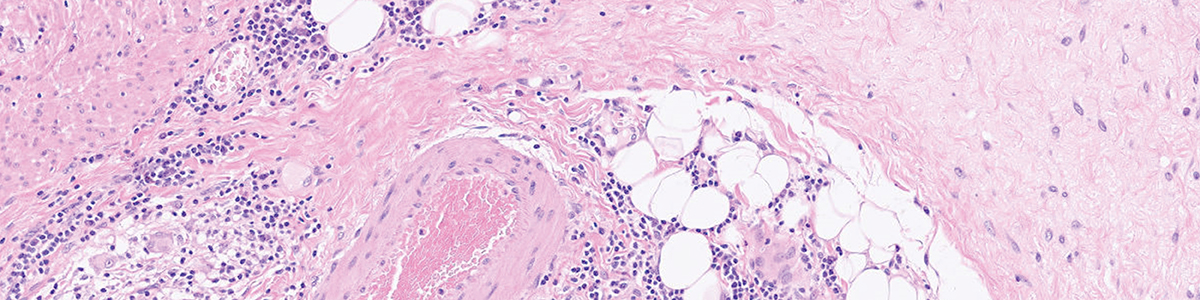

This theme day focuses on fixation and tissue processing, two essential steps for stable and high quality histology results. We explore approaches to improve fixation uniformity, reduce variation, and create reliable workflows that support diagnostics.

Together, we review practical methods, discuss common challenges, and share experiences from laboratories working with a wide range of specimen types.